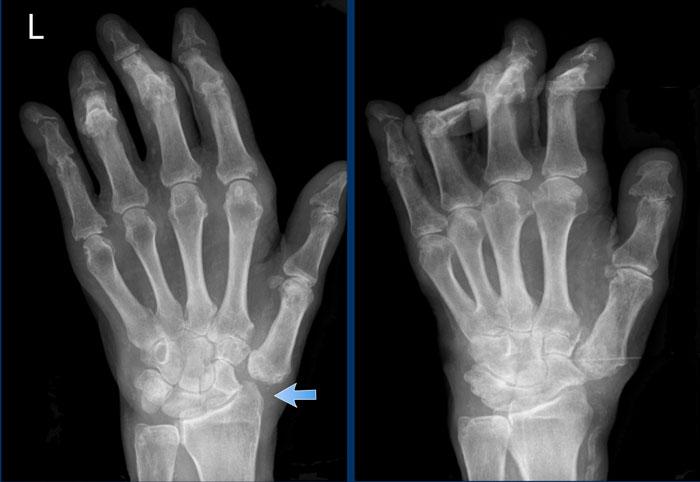

Ngón xúc xích

Hình ảnh điển hình của viêm ngón tay (dactylitis) “ngón xúc xích” với phù nề mô mềm và biến dạng bút chì trong cốc tại khớp liên đốt xa (DIP) 1-2 và 5 của bàn tay trái ở bệnh nhân viêm khớp vảy nến.

Lưu ý rằng các khớp bàn ngón tay (MCP) không bị tổn thương (khác với viêm khớp dạng thấp).

Viêm khớp vảy nến tiến triển

- Hình bên trái cho thấy bào mòn xương ở rìa khớp (mũi tên đen) và hình thành xương mờ nhạt (mũi tên xanh) tại khớp liên đốt ngón (IP).

- Về sau, bệnh tiến triển thành biến dạng bút chì trong cốc điển hình.

Phân bố tổn thương và sự hình thành xương khiến chẩn đoán viêm khớp dạng thấp ít có khả năng.

Các bào mòn xương ở rìa khớp và sự vắng mặt của tổn thương khớp liên đốt xa (DIP) ở các khớp khác khiến chẩn đoán viêm xương khớp bào mòn ít có khả năng, mặc dù biến dạng bút chì trong cốc có thể trông giống biến dạng cánh hải âu trong viêm xương khớp bào mòn.